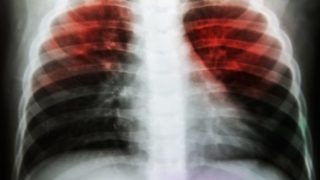

Some of the most effective home remedies for tuberculosis include the use of milk, pineapples, oranges, bananas, garlic, mint, walnuts, ...